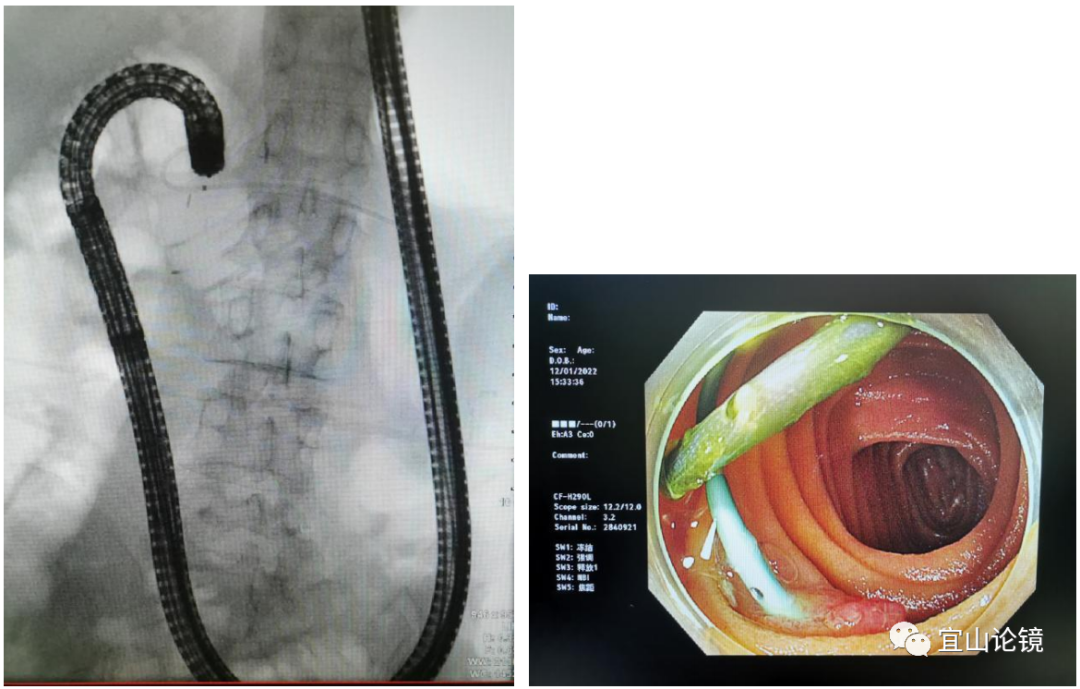

2)换1.6m肠镜带透明帽进镜,两侧对比寻找,选较难进镜及胆汁逐渐增多一侧,缓慢并反复拉直镜身,在X线辅助下,最终找见吻合口支架,拉直状态镜身距门齿约1.1m。

2)透明帽下压小肠皱襞,使吻合口面向镜头方向略倾斜,反转刀调整刀头向下,稳住镜身,对点对线导丝进入胰管。造影可见胰管扩张约0.9cm,狭窄段在吻合口处,未见明显充盈缺损,准备行吻合口扩张、胰管清理,最后放置多枚粗支架。